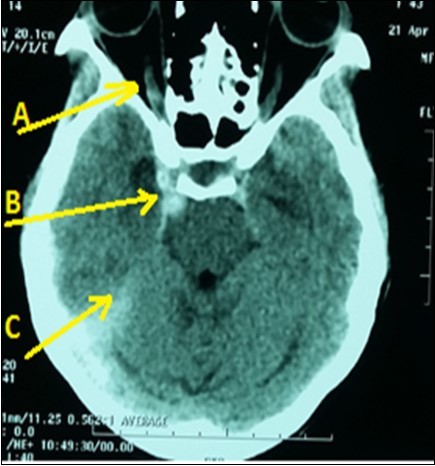

A 43-year lady, right-handed, single and mother of two children, was admitted in emergency neurology for intense headaches with vomiting, 2 generalized seizures and a sudden onset of consciousness disorders on April 19, 2016. Symptoms began two hours before her admission. She had no vascular history. The physical examination revealed intense headaches. The blood pressure was 130/80 mmHg with normal temperature (36.8 ° C). There was a light comas status with a Glasgow score of 12/15, a stiff neck, left hemiparesis and a bilateral Babinski reflex, right ptosis associated with reactive mydriasis, an exophthalmos and a total right ophthalmoplegia. Ophthalmologic examination revealed a right visual acuity of 1/10 with macular chorioretinitis. The brain CT scan (Figure 1) displayed a dilatation and hyper-density of right cavernous sinus with dilatation of the right ophthalmic vein associated with a subarachnoid hemorrhage. The routine biological tests were normal. An analgesic treatment had been administered in addition to nimodipine and mannitol (against brain edema) and clonasepam (against seizures). Unfortunately, as interventional neuroradiology and arteriography are not available, the patient had died on the seventh day of hospitalization in a context of increased intracranial hypertension.

Figure 1.Brain CT scan displaying right CCF (Arrow B) with subarachnoid hemorrhage (Arrow C) and right ophtalmic vein dilatation (Arrow A)